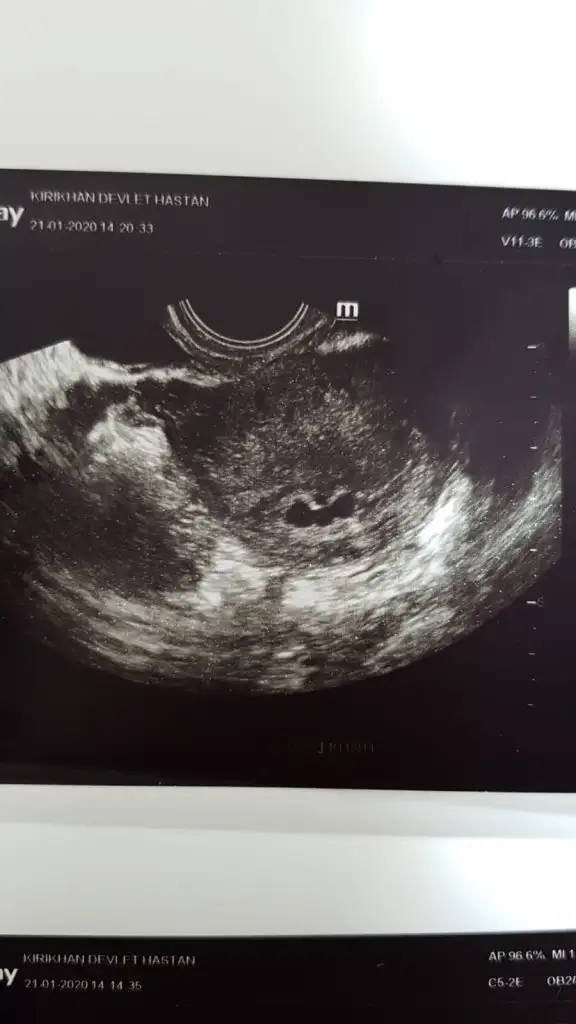

Ayrıca beni belki hatırlarsınız beta hcg değerlerim çok yüksekti, doktor keseyi görüp bebek görmediği için dış gebelik olabilir demişti ( Almanya’nın doktorları beni yedi)

Dün tekrar gittik ultrasonda , başta göremedi, yok sağlıksız filan dedi. Sadece kese var dedi, sonra minicik bi embriyo gördü üstelik kalp atımı bile var ..

Acayip canımız sıkıldı ama eşimle, yani o gün bebeği görmese muhtemelen bana sağlıksız deyip düşük için ilaç verecekti ..

6 haftalık , 5+6, 30 aralik transfer tarihim .

Bugünde üstten bakınca 1 alttan bakındica 3 kese gördü doktor ama çok yavaş gelişiyor dedi